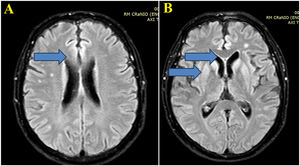

(A) Brain MRI images with Axial FLAIR sequence at the centrum semiovale show a small cortical hypersignal in the superior frontal gyrus bilaterally (blue arrow). (B) Brain MRI images at the basal ganglia level also demonstrate a symmetric and bilateral hypersignal in the caudate and putamen, as well as in the superior frontal gyri (blue arrow).

Case reportA 59-year-old man was diagnosed with HIV associated with Pulmonary Tuberculosis (TB) in late 2012 (at age 48) through ELISA and Western Blot serological tests, as well as a sputum culture for Acid-Fast Bacilli (AFB). He initially received treatment for TB, followed by Antiretroviral Therapy (ART) two weeks later, consisting of tenofovir (TDF), lamivudine (3TC), and efavirenz (EFV). Laboratory tests before starting ART showed a CD4 count of 18 cells/mcL (4 %) and a CD8 count of 203 cells/mcL (45 %), with a Viral Load (VL) of 224,906 copies/mL (Log=5.35). After completing TB treatment, his CD4 count increased to 167 cells/mcL (17.9 %), and his VL decreased to 82 copies/mL (Log=1.91). The patient developed Immune Reconstitution Inflammatory Syndrome (IRIS) with cervical lymphadenitis, which was managed with aspiration, and experienced persistent peripheral neuropathy during TB treatment, requiring pyridoxine supplementation. During this period, he also developed systemic arterial hypertension, type 2 diabetes mellitus, dyslipidemia, and keratitis related to past pterygium surgery. After 11-years of regular antiretroviral therapy, which was later switched to lamivudine and dolutegravir, he maintained persistent undetectable HIV viremia and adequate pharmacological control of systemic arterial hypertension, type 2 diabetes and hypercholesterolemia, using losartan 50 mg/day, metformin 1g/day, and atorvastatin 10 mg/day. He persistently reported bilateral 'boot distribution' paresthesia, attributed to an adverse reaction to isoniazid. During a routine follow-up on May 8, 2023, he mentioned that his partner had been complaining about him forgetting personal items, such as his wallet and car keys, despite the patient’s own disagreement. At this time the International HIV Dementia Scale scored seven points, and a brain MRI was recommended. Unfortunately, he did not undergo the requested brain MRI and returned only three months later, experiencing a sudden worsening of symptoms, including increased neuropathy, weight loss, social withdrawal, and somnolence. Neurological examination revealed temporal disorientation, ataxia, a left Babinski sign, hyperreflexia in the right patellar tendon, exhausted clonus in the right foot, and dysdiadochokinesia. Myoclonus was not present. Hospitalization was recommended, when evaluated by a neurologist, and MRI (in August 9) showed a restricted diffusion hypersignal located bilaterally in the insula, basal ganglia, and anterior cingulate cortex (Fig. 1). Seventeen days after this first and brief hospitalization, MRI showed symmetric and bilateral hypersignal in the caudate and putamen, as well as in the superior frontal gyri (Fig. 2). Concurrent laboratory tests showed no abnormalities, including a non-reactive VDRL and normal renal, thyroid, and liver function. A lumbar puncture was also performed, and partial analysis of the Cerebrospinal Fluid (CSF) revealed normal cell counts and glucose and protein levels. Tests for pyogenic bacteria, fungi, and tuberculosis and PCR for herpes simplex virus types 1 and 2 were all negative. RNA PCR for HIV in the CSF was also negative. In addition, CSF autoantibodies for autoimmune and paraneoplastic encephalitis and 14-3-3 protein analyses were requested. At this point, we suspected rapidly progressive dementia, with prion disease and immune-mediated encephalitis considered as the main possibilities. Due to the delay in obtaining the 14-3-3 protein results, the patient was hospitalized for pulse therapy with methylprednisolone (1.0 g/day for 5-days), followed by intravenous immunoglobulin (IVIG – 2.0 g/kg for 5-days). During the second hospitalization (lasted 56-days), repeat MRI showed the same abnormalities described above, but the patient’s condition worsened, with further memory decline, spastic tetraparesis, hypophonia, and bradykinesia in both the upper and lower limbs. Furthermore EEG video was performed due to its longer duration in an attempt to capture changes characteristic of CJD, such as triphasic waves. The disease progression was rapid, leading to a state of akinetic mutism. A Gastrostomy Tube (GTT) was placed due to dysphagia. The patient developed a fever caused by aspiration pneumonia, which was treated with antibiotics, and was discharged with the GTT, spastic tetraparesis and akinetic mutism. After 60-days, the 14-3-3 protein results were received, revealing high titers, and the family was consulted about initiating palliative care to avoid invasive measures. During his course, the patient underwent 3 EEGs, all of which revealed only nonspecific slowing. RT-QuIC analysis of the CSF was positive. He passed away 6-months after the onset of neurological symptoms.